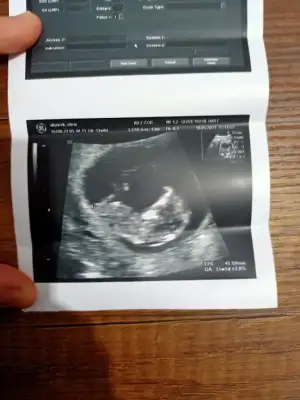

dr soylemeden siz gorun genital nub teorisi ( bebegin cinsiyeti)

Merhaba arkadaslar,aslinda bebegimin cinsiyeti belli,dr.eşime kağıda yazıp verdi ama eşim pazar gunu surpriz yapacagi icin bana søylemiyor,sizin bi tahmininiz varmı?Merakdan çatliyorum.😄😊Eki Görüntüle 2848569

Emin olmadım ama sanki kız gibi geldi bana 🙈 en iyi 11 12 13 haftalar olmalı yada başka USG varsa paylaşın 🤗

Ikra hanım merhaba 11+1den karından usg atıyorum rica etsem tahminde bulunur musunuz arkadaşım için bana kız demiştiniz doğru cıktı 🤭😊